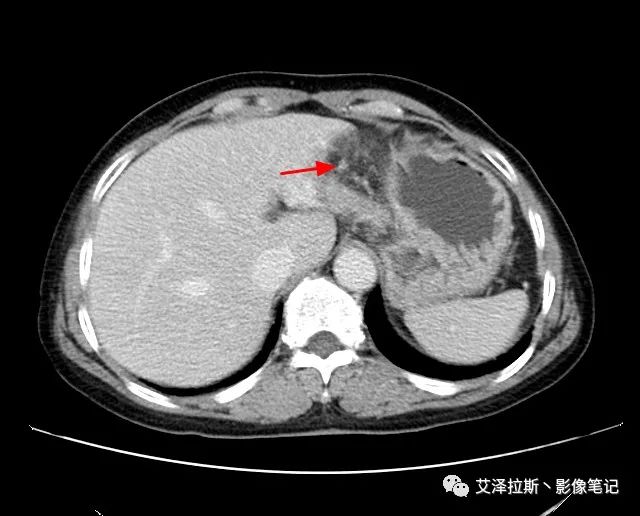

【影像所見】 胃竇部狹窄,胃壁環形增厚,小彎側見一巨大潰瘍,周圍伴“環堤征”,漿膜面不完整,胃周脂肪見網格狀條索影,病灶與肝臟左葉、胰腺鉤突脂肪間隙消失,增強掃描病灶明顯強化。引流區內約15個區域淋巴結受累。

【診斷意見】 胃竇部胃癌(T4N3期) 該病例腫塊突破漿膜層,與肝臟左葉、胰腺鉤突分界不清,脂肪界面消失,定為T4期; 受累及的淋巴結為15個區域,定為N3; 有無遠處轉移尚不明確,所以M期暫時無法確定。